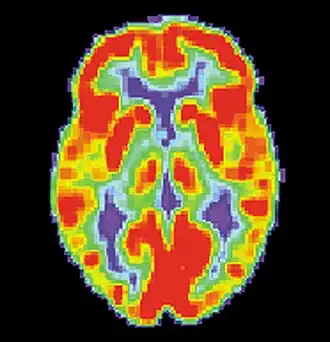

Neural systems used by procedural memory are commonly targeted by Human Immunodeficiency Virus; the striatum being the structure most notably affected.[64] MRI studies have even shown white matter irregularity and basal ganglia subcortical atrophy in these vital areas necessary for both procedural memory and motor-skill.[65] Applied research using various procedural memory tasks such as the Rotary pursuit, Mirror star tracing and Weather prediction tasks have shown that HIV positive individuals perform worse than HIV negative participants suggesting that poorer overall performance on tasks is due to the specific changes in the brain caused by the disease.[66]

Huntington's disease

Despite Huntington's disease being a disorder that directly affects striatal areas of the brain used in procedural memory, most individuals with the condition display different memory problems from people with striatum related brain diseases.[67] In more advanced stages of the disease, however, procedural memory is affected by damage to the important brain pathways that help the inner subcortical and prefrontal cortex parts of the brain to communicate.[68]